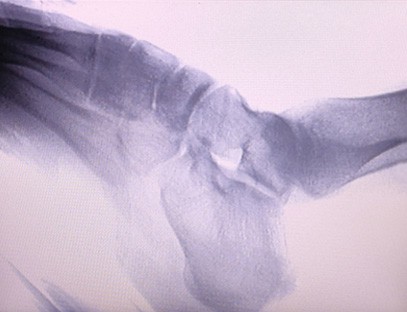

Przenośny aparat rentgenowskijest niskodawkowym, bardzo bezpiecznym przenośnym instrumentem, który może uzyskać wysokiej jakości obrazy przy jednoczesnym zmniejszeniu narażenia na promieniowanie. Kompensuje niedociągnięcia dużego sprzętu szpitalnego i może być przenoszony i transportowany w dowolnym momencie. Szczególnie nadaje się do jednostek i osób o niewystarczającym budżecie i niskich wymaganiach dotyczących obrazów. Nasz aparat rentgenowski nowej generacji jest wyposażony w 10-calowy duży ekran o wysokiej rozdzielczości, który ma większy zakres kąta widzenia i może w pełni zobaczyć całą dłoń, w tym złamania, zwichnięcia, zapalenie stawów i guzy kości. Można go podłączyć do drukarki filmowej w celu drukowania filmów ortopedycznych, a także można go używać do produkcji przemysłowej i testów. Nie ma potrzeby ciemni, bezpośredniej perspektywy, obserwacji w czasie rzeczywistym. Ten aparat ma system obrazowania o wysokiej rozdzielczości, który może bardzo wyraźnie rejestrować obrazy dowolnej struktury kostnej. Aby zapewnić najlepszy sprzęt do badań rentgenowskich i rozwiązania dla producentów wyrobów medycznych, weterynaryjnych, przemysłowych, elektronicznych, działów kontroli i konserwacji oraz laboratoriów badawczych.

Specjalizacja:Zaprojektowany z myślą o potrzebach klinik ortopedycznych, szczególnie odpowiedni dla:Obrazowanie rentgenowskiekończyn takich jak: dłonie, nadgarstki, łokcie, ramiona, kolana, kostki itp.

Wyraźne obrazowanie:Zaawansowana technologia obrazowania cyfrowego jest wykorzystywana do wykonywania wysokiej jakości zdjęć rentgenowskich, pomagając lekarzom w dokładnym diagnozowaniu schorzenia.